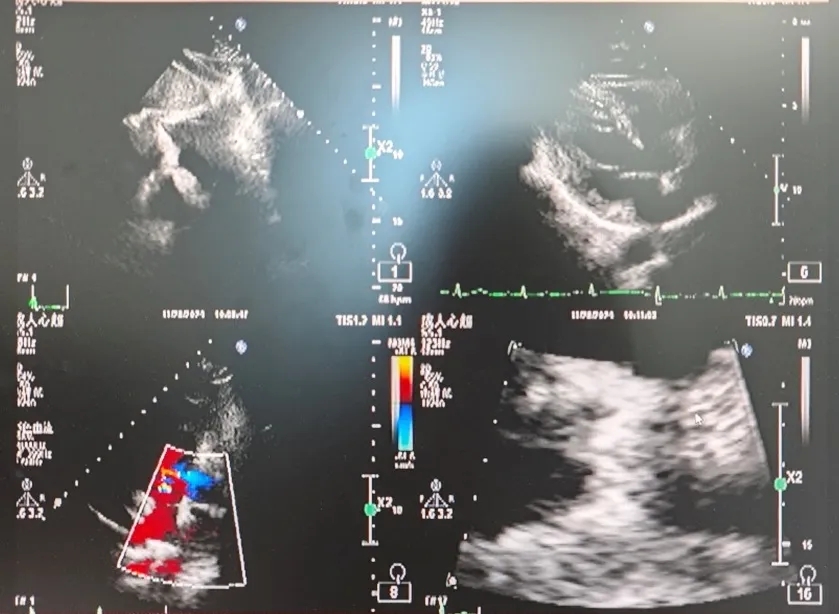

超声所见:经食管超声心动图+灰阶三维成像+彩色三维成像:卵圆孔未闭可吸收封堵器置入术后:未见残余分流,可吸收封堵器位置回声与心肌组织回声接近。

超声结论:未见残余分流。

超声所见:右心声学造影:两支10ml注射器,分别抽取1ml空气和8ml生理盐水,经三通管相连,回抽1ml静脉血,使三者在2支注射器间反复推注10次以上,充分混合后置于1支注射器内,将配置好的造影剂快速经右肘正中静脉推注后,右房、右室即刻微泡显影,左房、左室未见显影,嘱患者经瓦氏动作,左房、左室仍未见微泡影。

超声结论:右心声学造影:阴性(无右向左分流)。